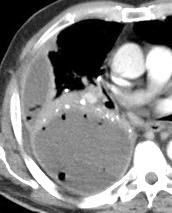

Engrosamiento de la pleura parietal 36/ 59 exudados (61%) 56% de D. paraneumónicos 100% de empiemas Especificidad.. 96%.

Exudado versus trasudado.

Aquino SL, et al. Pleural exudates and transudates: diagnosis with contrast-enhanced CT. Radiology 1994

Signo de la Pleura separada “Split pleural sign”

Capas pleurales de grosor uniforme realzadas por el contraste

Dr. César Pedrosa

No específico de empiema. Indica “exudado”. 68% de pacientes con empiema pleural.

Capas pleurales de grosor uniforme

Realce grasa extrapleural (30%)

> Grasa Extrapleural. (60-80%)

Kraus GJ. Split pleural sign. Radiology 2007

Pleural visceral 50%

Pleural parietal 100%

Walker CM et al. Imaging Pulmonary Infection: Classic Signs and Patterns. AJR. 2014/Stark DD, et al. Differentiating lung abs cess and empyema: radiography and computed tomography. AJR. 1983